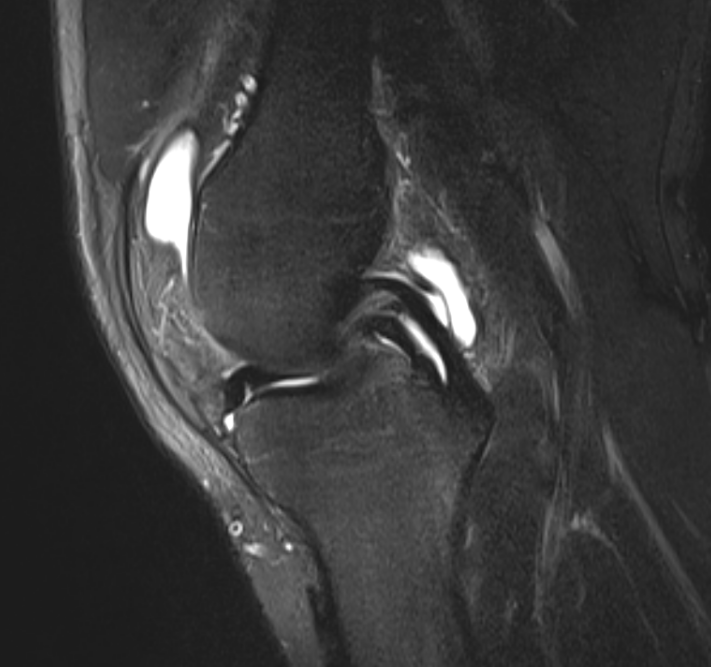

Double PCL sign